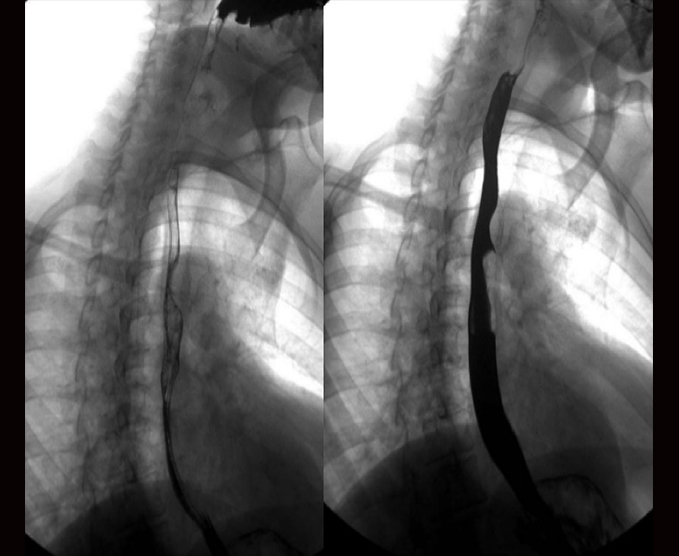

Algunos de nuestros estudios contrastados.

- Serie esófago gastroduodenal

- Esófagograma